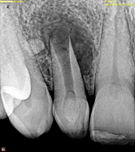

Perfurações dentarias são complicações no tratamento de canal que na maioria dos casos resulta em um prognóstico desfavorável, pois permite a entrada de microrganismos nos tecidos que envolvem o dente. Em alguns casos, devido ao seu difícil diagnóstico, acesso limitado, tempo decorrido ou tamanho da perfuração resultará em um desafio para o profissional conseguir um selamento adequado da área, sendo muito importante o conhecimento sobre o material que será empregado.